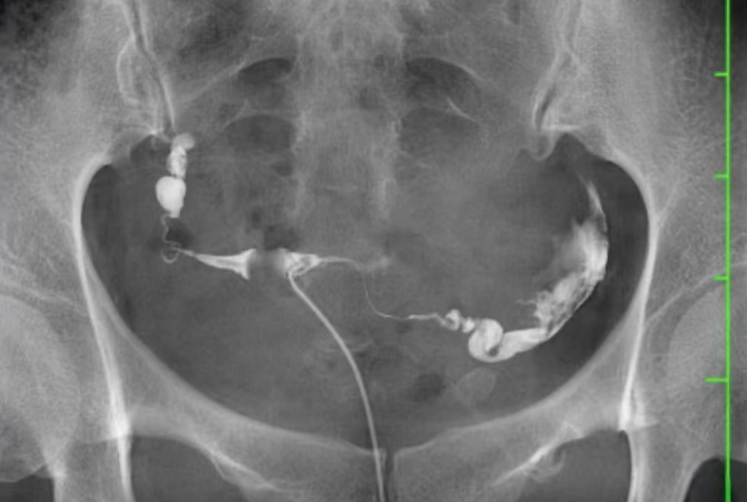

2.输卵管放射造影(HSG)

①核心成像原理——利用含碘造影剂,通过X线(放射)设备拍摄影像,观察造影剂分布。

②造影剂类型——含碘溶液(如碘海醇、碘油等,有放射性)。

④检查优势——影像分辨率高,对输卵管阻塞部位、形态的显示更清晰;部分含碘造影剂(如碘油)有轻微“疏通输卵管”的辅助作用。